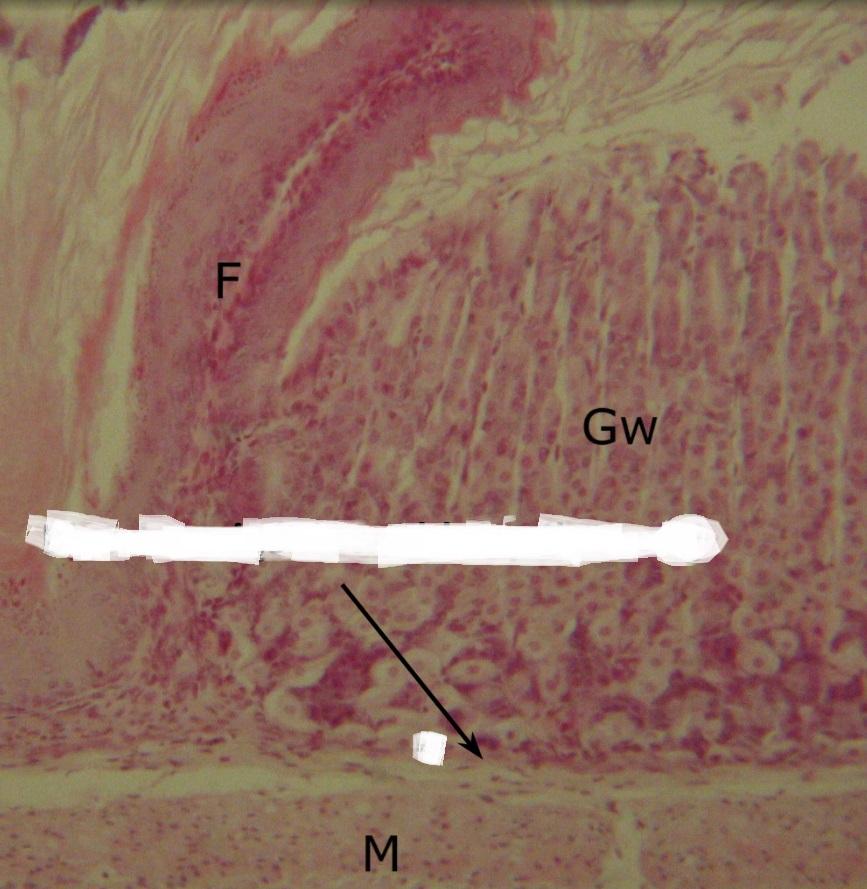

Pytanie 383

błona mięśniowa przełyku (przejście przełyku w żołądek)

Pytanie 384

fałd błony śluzowej (przejście przełyku w żołądek)